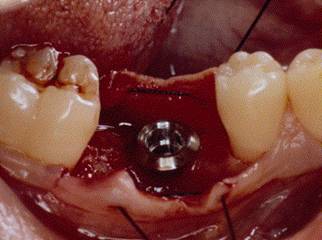

IMPLANT IN SITU

ABUTMENT PLACEMENT